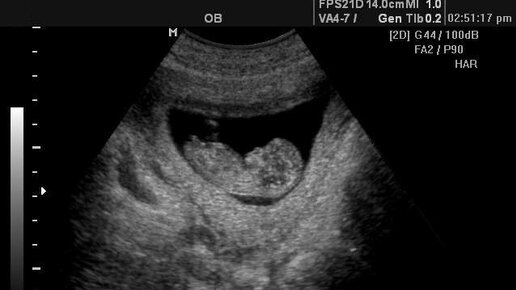

Фото узи девочки на 1,2 и 3 скрининге💐

11 неделя беременности — назначают УЗИ плода

Одиннадцатая неделя беременности На 11 неделе четверть беременности позади, а вас все так же тошнит по утрам, хотя, возможно, уже меньше. Животика еще нет, но любимые узкие джинсы неприятно жмут в талии. На 11 неделе, как правило, назначается УЗИ плода, где измеряется его копчиково-теменной размер (сокращенно КТР), а также воротничковое пространство (ВП). Данные показатели крайне важны для оценки развития будущего малыша и исключению некоторых врожденных пороков развития. Будущий ребенок развивает...